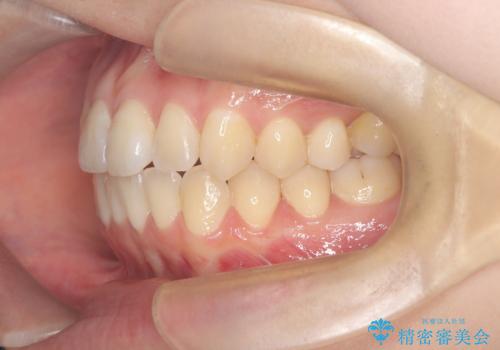

下顎前歯の叢生が整い、右下5番部には機能的かつ審美的なインプラント補綴が完了しました。

咬合全体のバランスも改善し、長期的な安定性が期待される状態となりました。

患者様にも「長年気になっていた前歯のがたつきも一緒に治せてよかった」と喜んでいただけました。